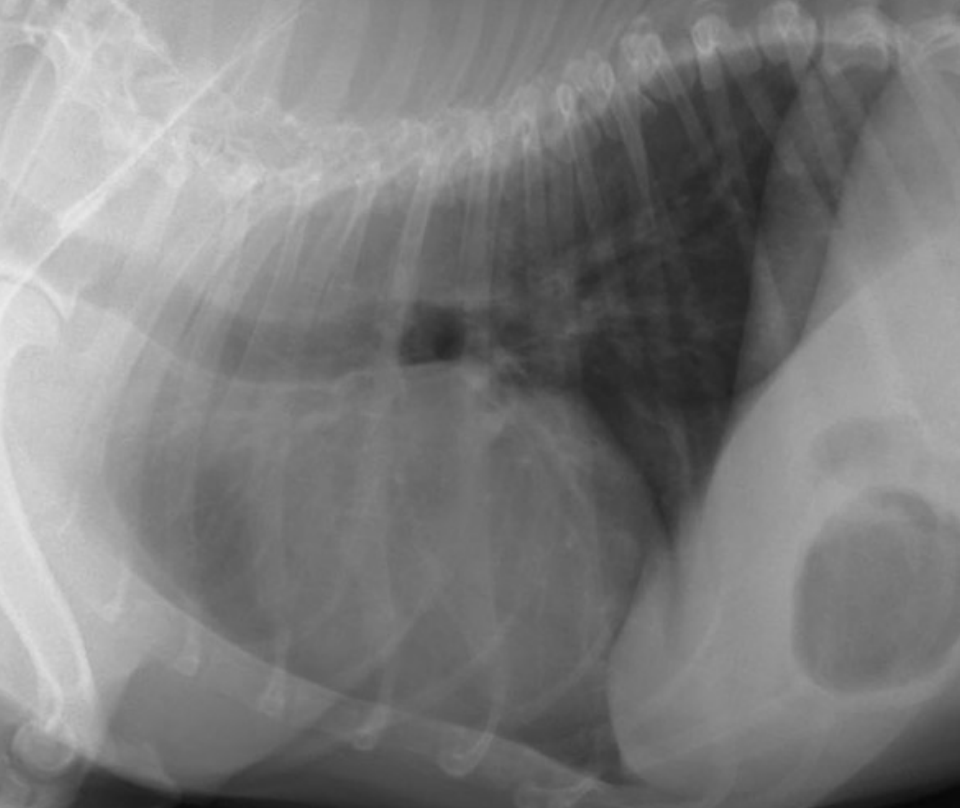

What is shown in this image?

A